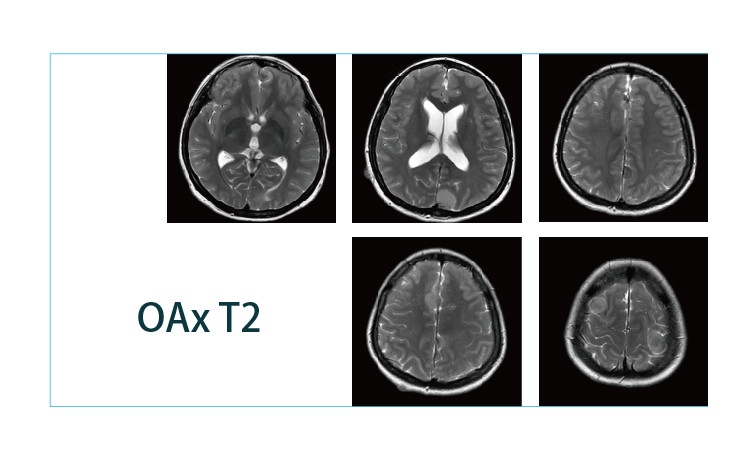

【朗润影像档案】磁共振影像病例分享(编号20190412)